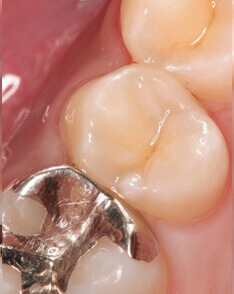

ダイレクトボンディング 治療後

術後

ダイレクトボンディング治療後